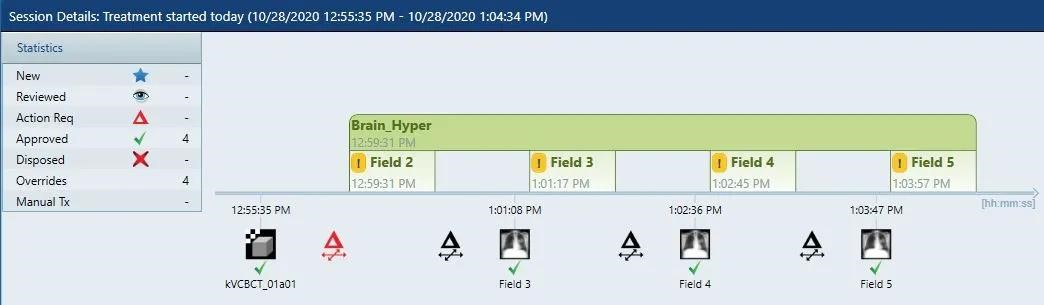

2020年10月28日,首例HyperArc治疗开展,全程共10分钟,其中出束开始到治疗结束不到5分钟。因为治疗的高度自动化,技师无需进入治疗室重新对患者进行摆位或者手动移床,治疗时间远远低于常规非共面治疗。